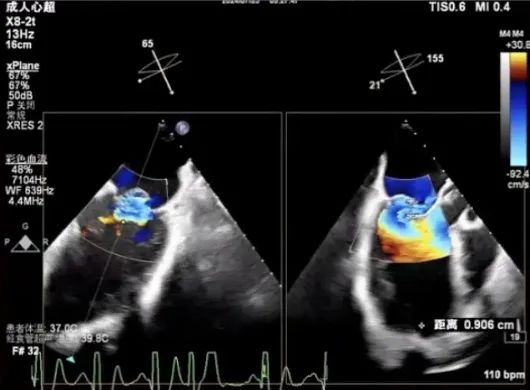

手术操作

术中观测,卵圆窝范围较小,解剖位置偏下偏前;即便选择其最靠后的位置进行穿刺,穿刺高度仍受限制。

最终穿刺高度受限,仅3.3cm

穿刺位点良好,3点钟

置入CDS并调整位置与方向,操作过程中调整M键向“+”键方向旋转,使大鞘头端指向二尖瓣环,此时尚未完全完成骑跨。术中经TEE观察可见,因左房空间受限、穿刺高度不足,CDS已跨过二尖瓣。